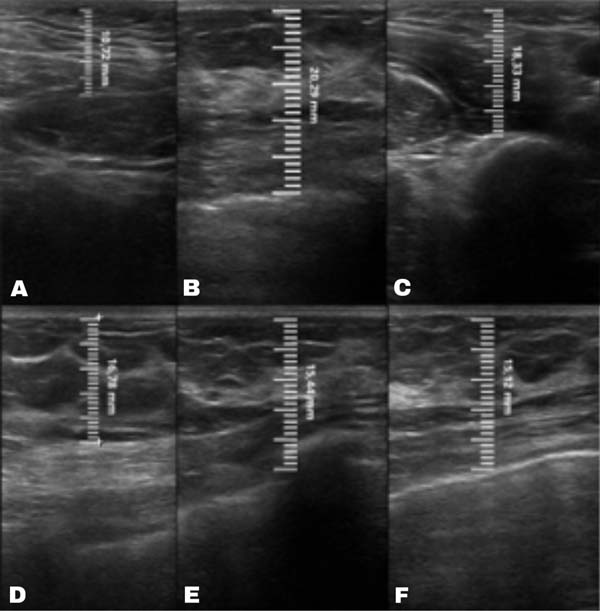

No grupo enxerto decantado, a reducãomédia, comparando-se a espessura inicial apos lipoenxertia, foi de 9,90% no 15° dia, 19,27% no 1° mes, 23,59% no 3° mes e 26,36% no 6° mes. No grupo enxerto filtrado, a reducao media, comparando-se a espessura inicial apos lipoenxertia, foi de 7,74% no 15° dia, 14,85% no 1° mes, 20,67% no 3° mes e 22,80% no 6° mes. ►Fig. 6. A evolução ao ultrassom da espessura do tecido subcutâneo antes e depois da lipoenxertia pode ser vista nas ►Figs. 7-8. Os resultados de pré-e pós-operatório de uma paciente de cada um dos grupos estão exibidos nas ►Figs. 9-10.

Fig. 7 - Ultrassonografia grupo gordura decantada: (A) Pre-operatorio: 10,02 mm. (B) Pós-operatOrio imediato: 23,82 mm. (C) 15 dias depOós-operatório: 22,03mm. (D) 1 mês de pos-operatorio: 20,14mm. (E) 3 meses de pos-operatorio: 18,12mm. (F) 6 meses de pos-operatorio: 17,32mm.

Fig. 8 - Ultrassonografia grupo gordura filtrada: (A) Pre-operatorio: 10,72mm | (B) Pos-operatorio imediato: 20,29mm. (C) 15 dias de pos-operatOrio: 18,33 mm. (D) 1 mês de pos-operatorio: 16,78 mm. (E) 3 meses de pos-operatorio: 15,44 mm. (F) 6 meses de pos-operatorio: 15,12 mm.